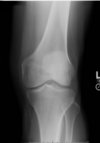

Q

Which of the following would correct the positioning error demonstrated?

1 - Direct the CR more medially

2 - Rotate knee 5-10° externally

3 - Angle CR 5-10° caudad to level tibia plateaus

A - 2 only

B - 1 and 2 only

C - 2 and 3 only

D - 1 and 3 only

A

The correct answer is B.

The AP knee above has part rotation and has slightly askew centering. To correct for these positioning errors, the patient’s knee should be centered more medially (1) in order to reduce medial soft tissue cutoff. The knee should also be rotated 5-10° externally. The knee is currently rotated internally, thus visualizing the proximal tibiofibular articulation. If angulation were to be used, a cephalic angulation of 5-7° could be applied to level the tibial plateaus (3).